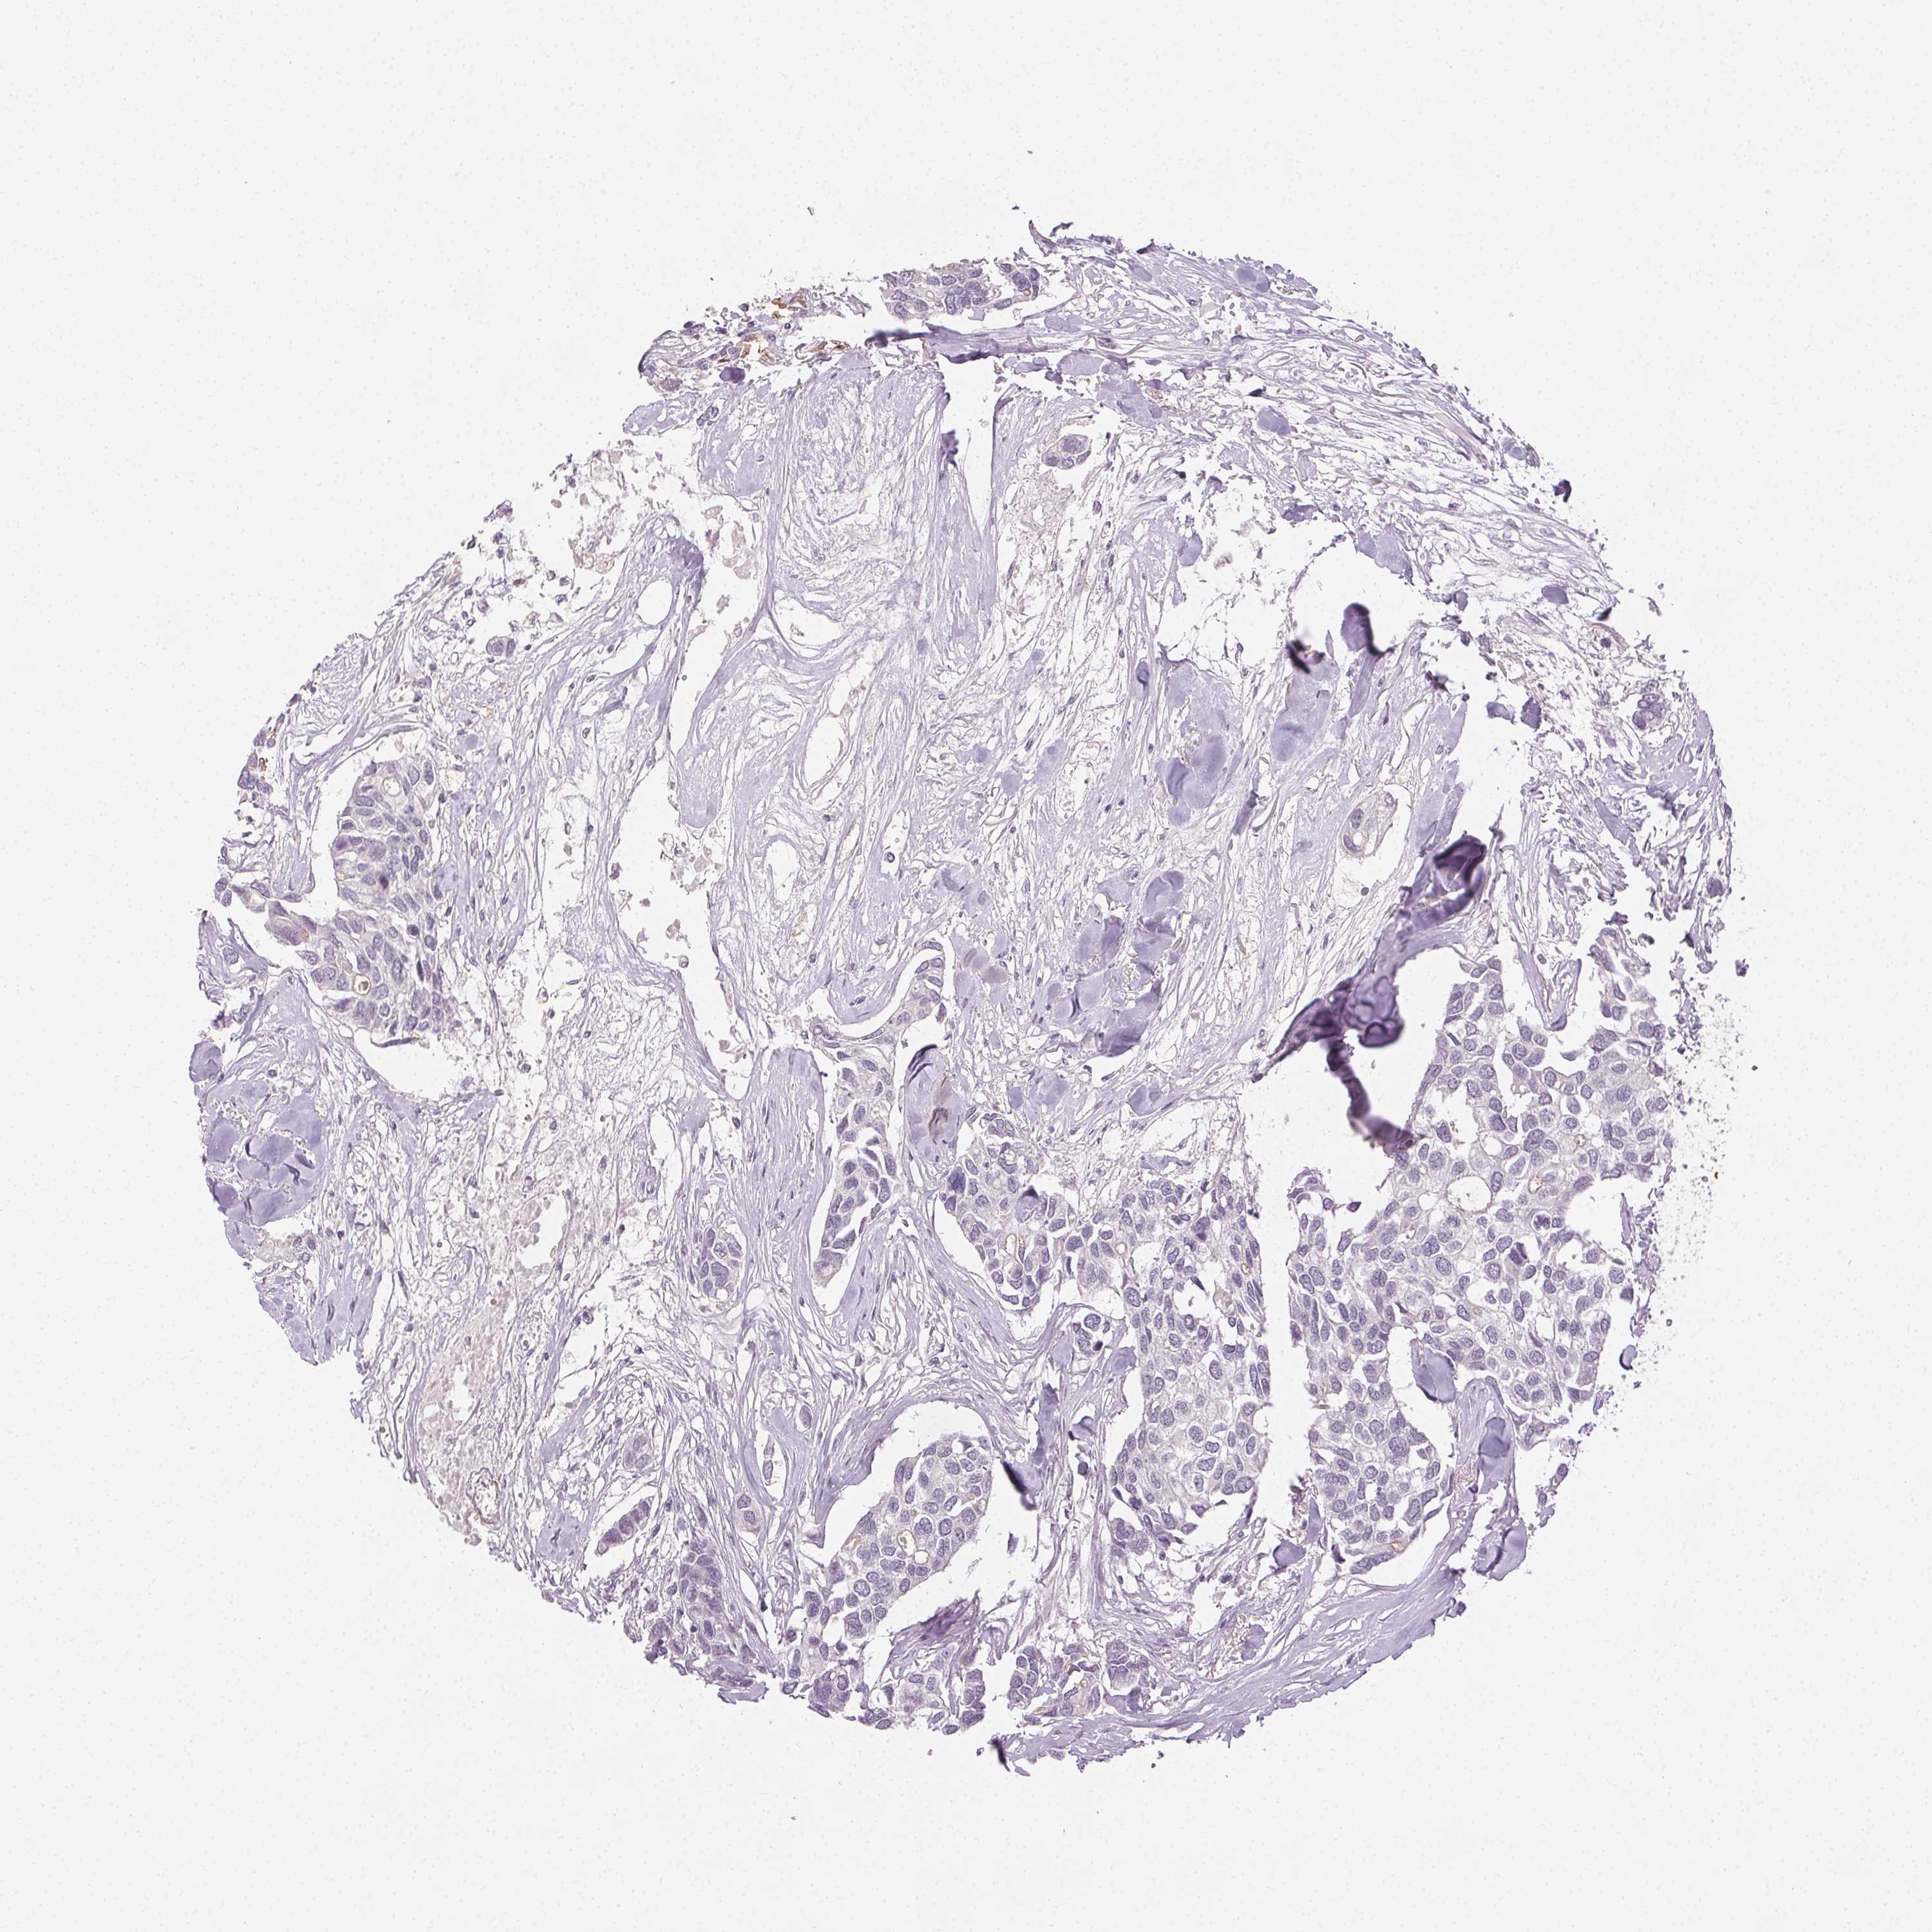

CANCER BREAST CANCER Show tissue menu

BRCA TCGA BRCA VALIDATION PROTEIN EXPRESSION